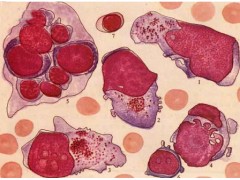

肝癌,RH-35

【规    格】1株/1ML

【储存条件】低温保存

【产品商标】ATCC

【供应限制】仅供科研使用